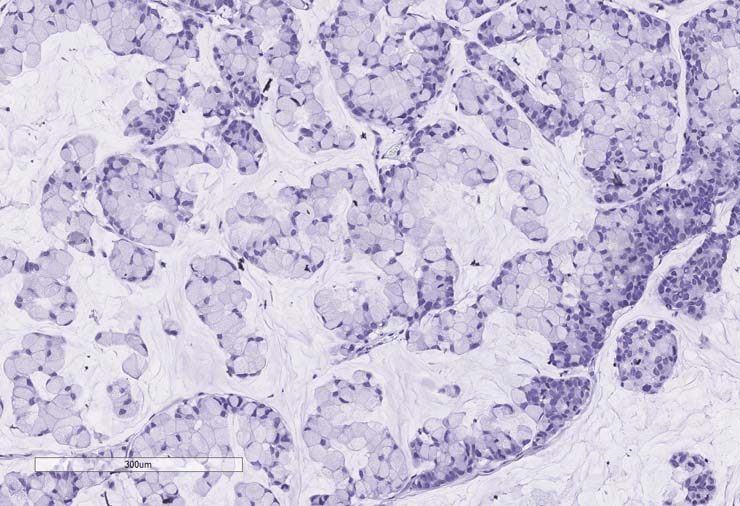

P0 tumor F240 for PDX model TM00351 stained for CD45. Staining was negative.

P1 tumor F239 ID003 for PDX model TM00351 stained for CD45. Staining was positive.

P2 tumor F239 ID011 for PDX model TM00351 stained for CD45. Staining was negative.